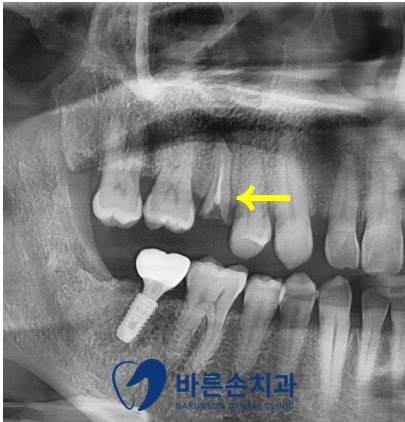

환자분의 경우 발치 당일 임플란트 수술이 가능한 케이스였기에

내원 당일 바로 수술을 진행하여

보다 쉽고 빠른 치료를 기대해 볼 수 있습니다